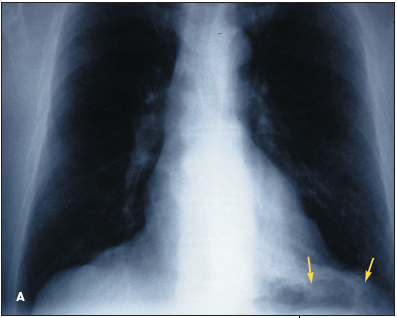

Routine chest radiographs reveal a left lower lobe density in a 70-year-old man (Figure 1 - Posteroanterior (A) and lateral (B) chest radiographs demonstrate a density in the left lower lobe). He has no chest pain, dyspnea, or hemoptysis.